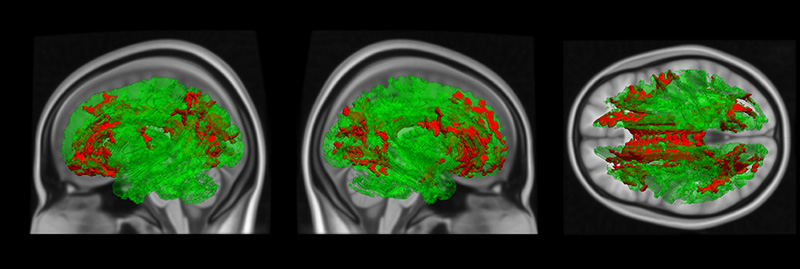

Рис.1. Области статистически значимого (p<0.025 с учетом коррекции на множественные сравнения) снижения фракционной анизотропии в различных областях головного мозга в группе больных юношеской приступообразной шизофренией (26 пациентов) по сравнению с психически здоровым контролем (42 40 человека).